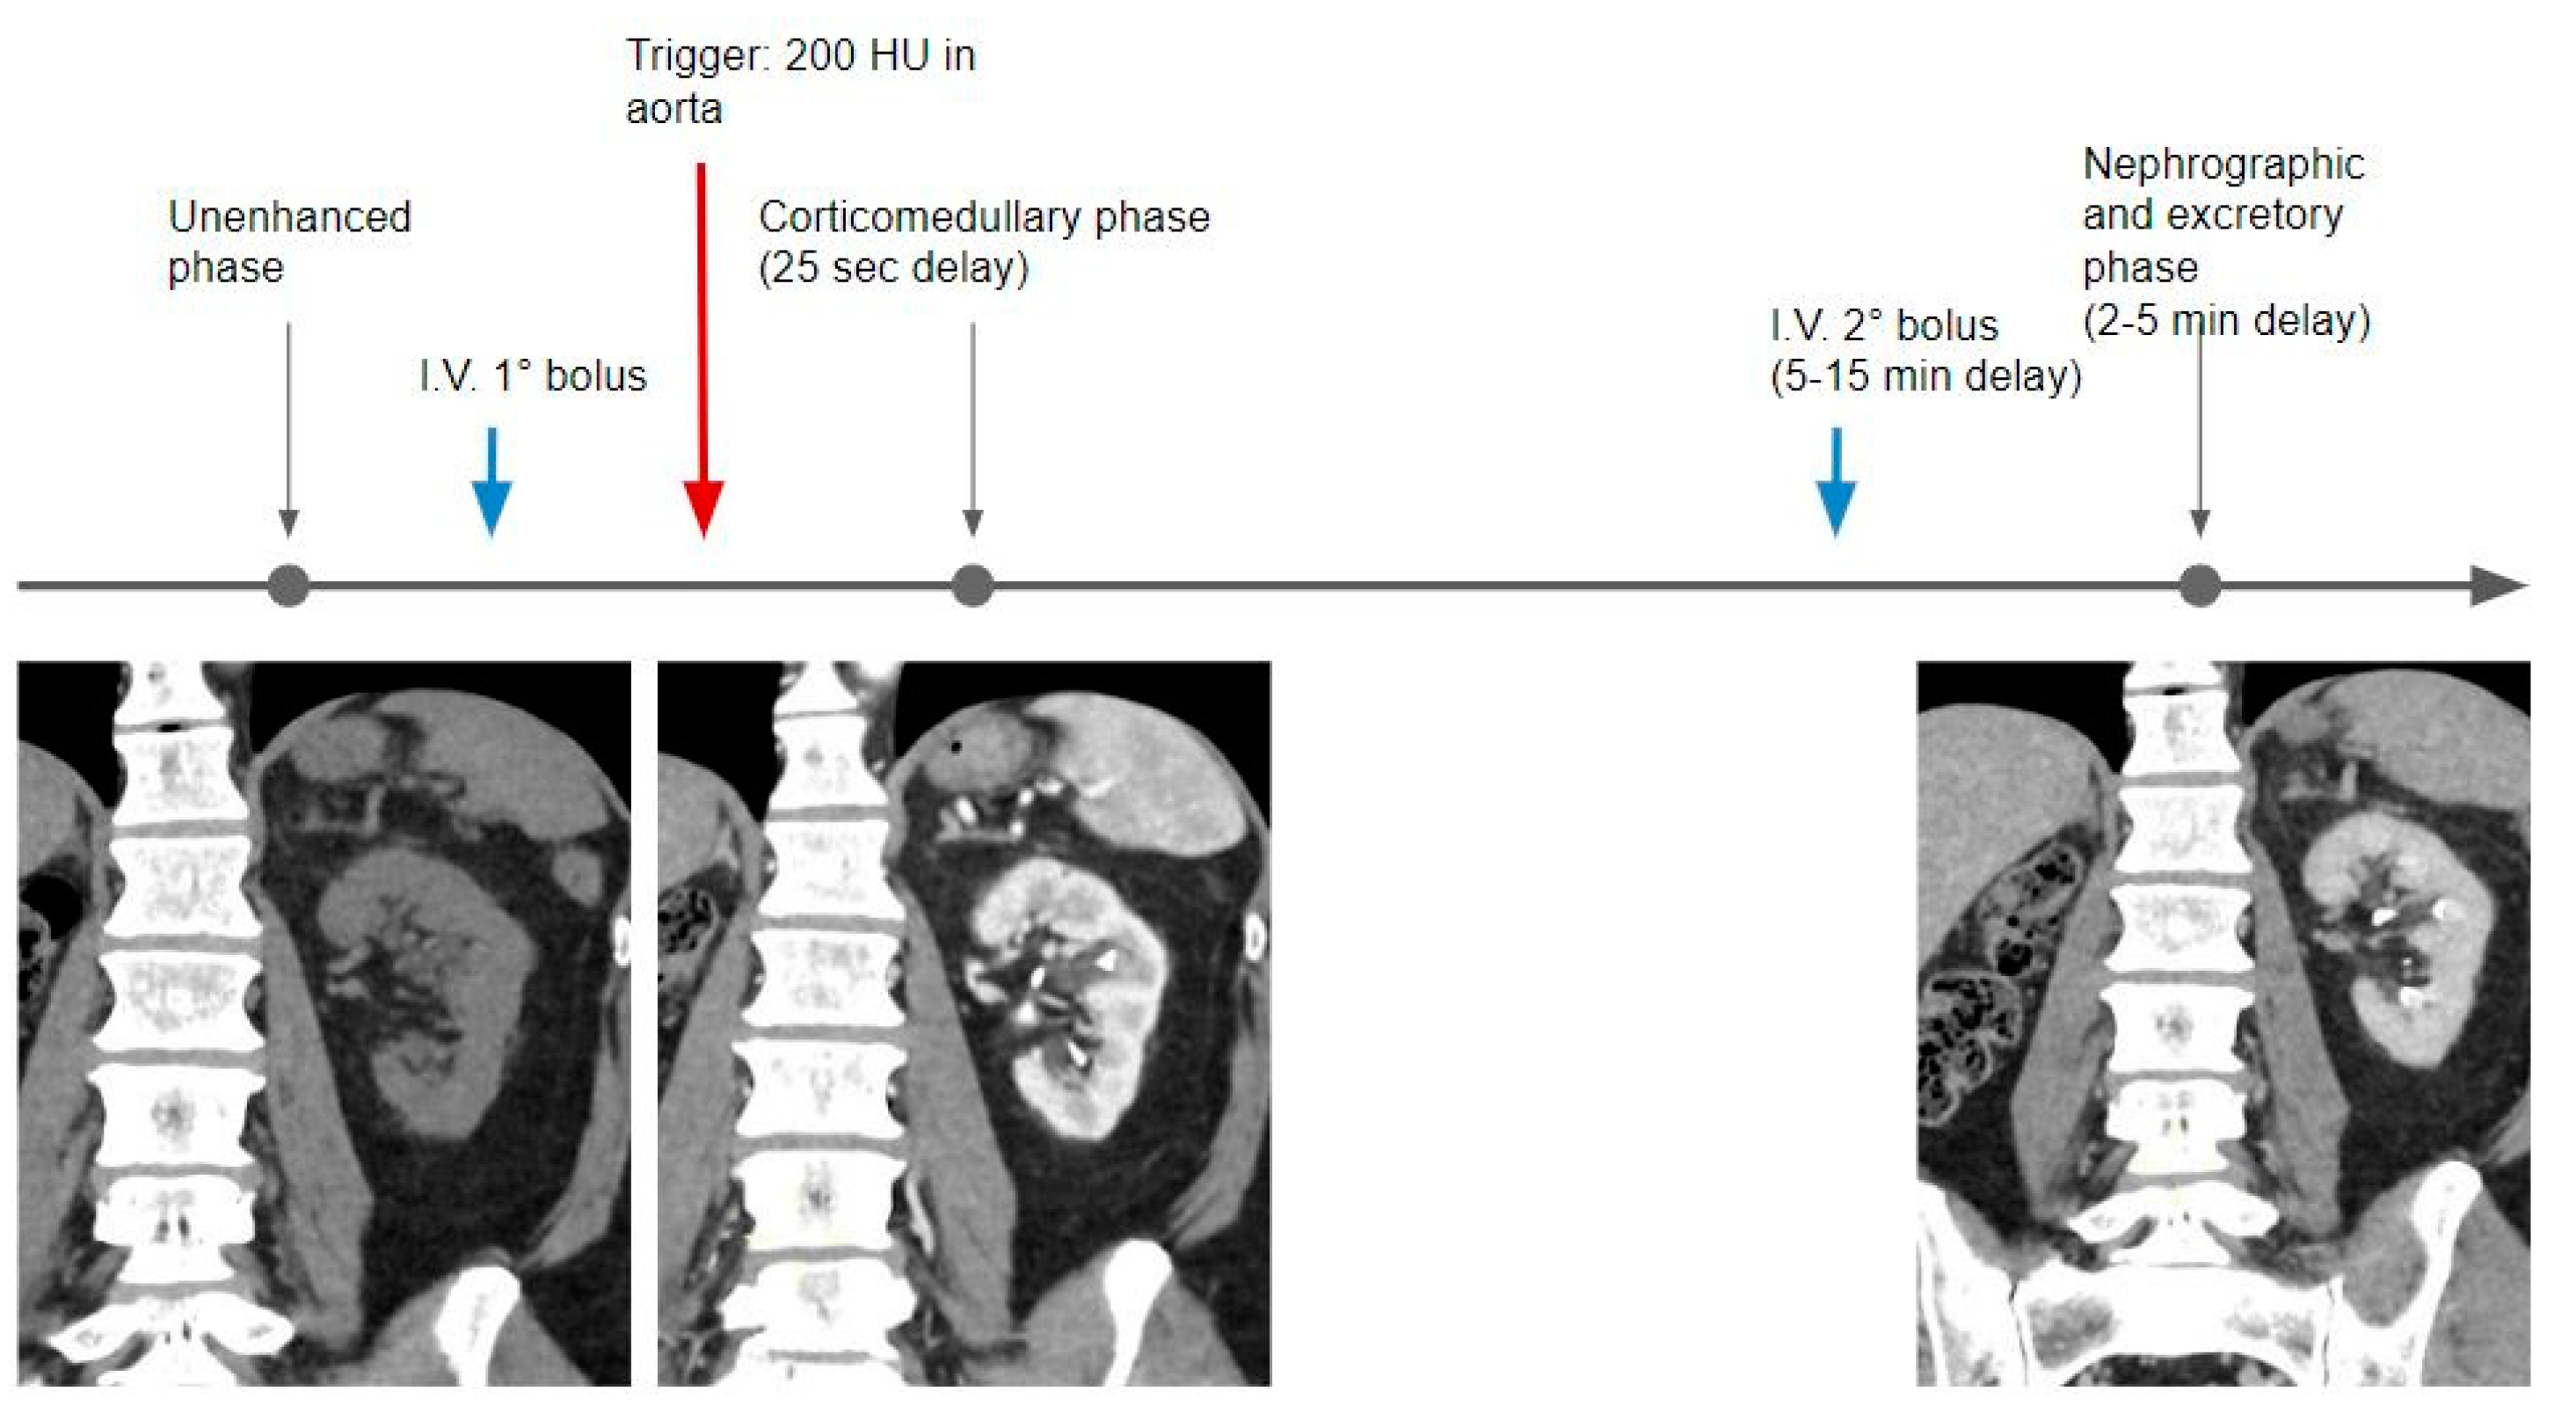

The traditional study technique includes the acquisition of a non-contrast phase, followed by the injection of the full dose of contrast medium and acquisition of the nephrographic (80 to 120 s) and delayed excretory phases (5 to 15 min); additional acquisition of the CMP (30 to 40 s) is optional [18] (Table 2) (Figure 3).

Figure 3.

Graphical representation of the single bolus acquisition technique.

The first acquired phase is the CMP, usually acquired with a bolus tracking technique, placing a region of interest in the abdominal aorta, with a threshold of 200 HU, with an estimated acquisition delay set at 25 s. In this phase, the kidney contrast enhancement is related to the arterial inflow. The nephrographic phase is then acquired at a delay of about 40 s when the renal parenchyma is almost homogeneous in density.

In the excretory phase, the renal parenchyma is homogeneous but characterized by a markedly reduced density in comparison with the previous phases, with the calyces and pelvis filled with iodinated urine.

In the split bolus technique, the nephrographic (for the detection of renal masses) and excretory phases (for urothelial neoplasms) are acquired at the same time, avoiding one acquisition, and thereby reducing the radiation dose by approximately one-third (Figure 4).

Figure 4.

In the split bolus technique, after the unenhanced phase, the first portion of the whole contrast medium dose is administered (usually one-third or half); then, using the bolus tracking technique and a delay of 25 s, the corticomedullary phase is acquired. A second bolus of contrast medium is injected at a variable timing (5–10 min of delay), followed by a third CT acquisition, where the kidneys are in the nephrographic phase and the calyces and pelvis are filled with iodinated urine.

In this protocol, the contrast bolus is administered in two separate injections. After the unenhanced phase, the first part (usually one-third or half) of the contrast is injected and the optional CMP is obtained, then the second part of the contrast (usually a dose larger than or equal to the first one), is injected about 5–10 min later, and combined nephrographic–excretory phase images are acquired at 2–5 min when the kidneys show enhancement of the renal parenchyma and opacification of the collecting systems occurs [7] (Table 2).

The triple bolus technique is performed in a few institutions and is based on the separation of the total contrast volume into three injections. An optional unenhanced phase can be acquired, the first bolus part is then injected, followed by a delay time, the second bolus part is then injected, a delay time elapses, then the third portion of the bolus is administered, and finally, post-contrast images are acquired. The resulting acquisition combines CMP, nephrographic, and excretory phases, allowing simultaneous arterial, parenchymal, and collecting system enhancement (Figure 5).

Figure 5.

The contrast medium dose is divided into three parts: the first one is administrated after the non-contrast acquisition; the second bolus is injected after a variable time delay (5–15 min); and then a third bolus at 100 s of delay, followed by the acquisition of a mixed corticomedullary and excretory phase.

This protocol significantly decreases the total radiation dose because of the reduction in the total number of acquired contrast phases; however, due to the bolus splitting, only a portion of the total contrast medium volume contributes to excretory imaging, thus resulting in potential limited distension and opacification of the ureters.

This protocol also provides limited accuracy in renal cell carcinoma detection, due to the absence of a dedicated arterial phase image acquisition, which is the most sensitive to clear cell renal cell carcinomas [7].